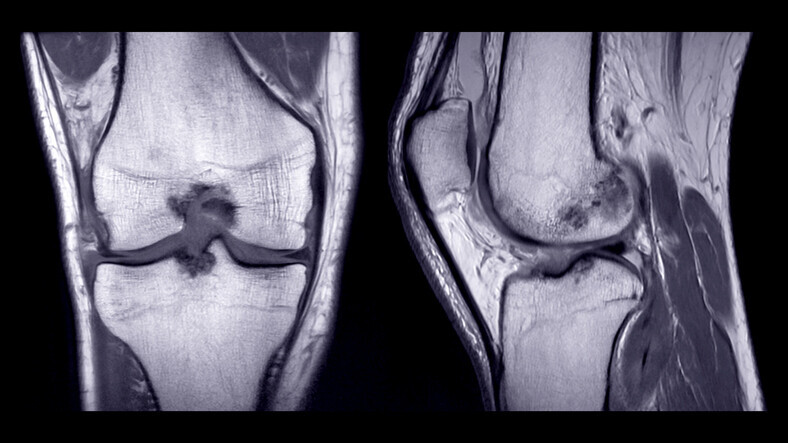

Chronic Joint & Tendon Pain Embolization - Image 4

What tests are needed?

We need to image the affected area to see exactly what the problem is, either with ultrasound, MRI or X-rays.

Early knee osteoarthritis (KL grades 1 & 2) has exactly the same in growth of abnormal blood vessels and pain fibres. When pain killers are no longer working, but the patient is too young for joint replacement, MSKE is good treatment to reduce pain and postpone joint replacement surgery.

MSKE for the knee osteoarthritis is also known as ‘Geniculate Artery Embolization (GAE)’